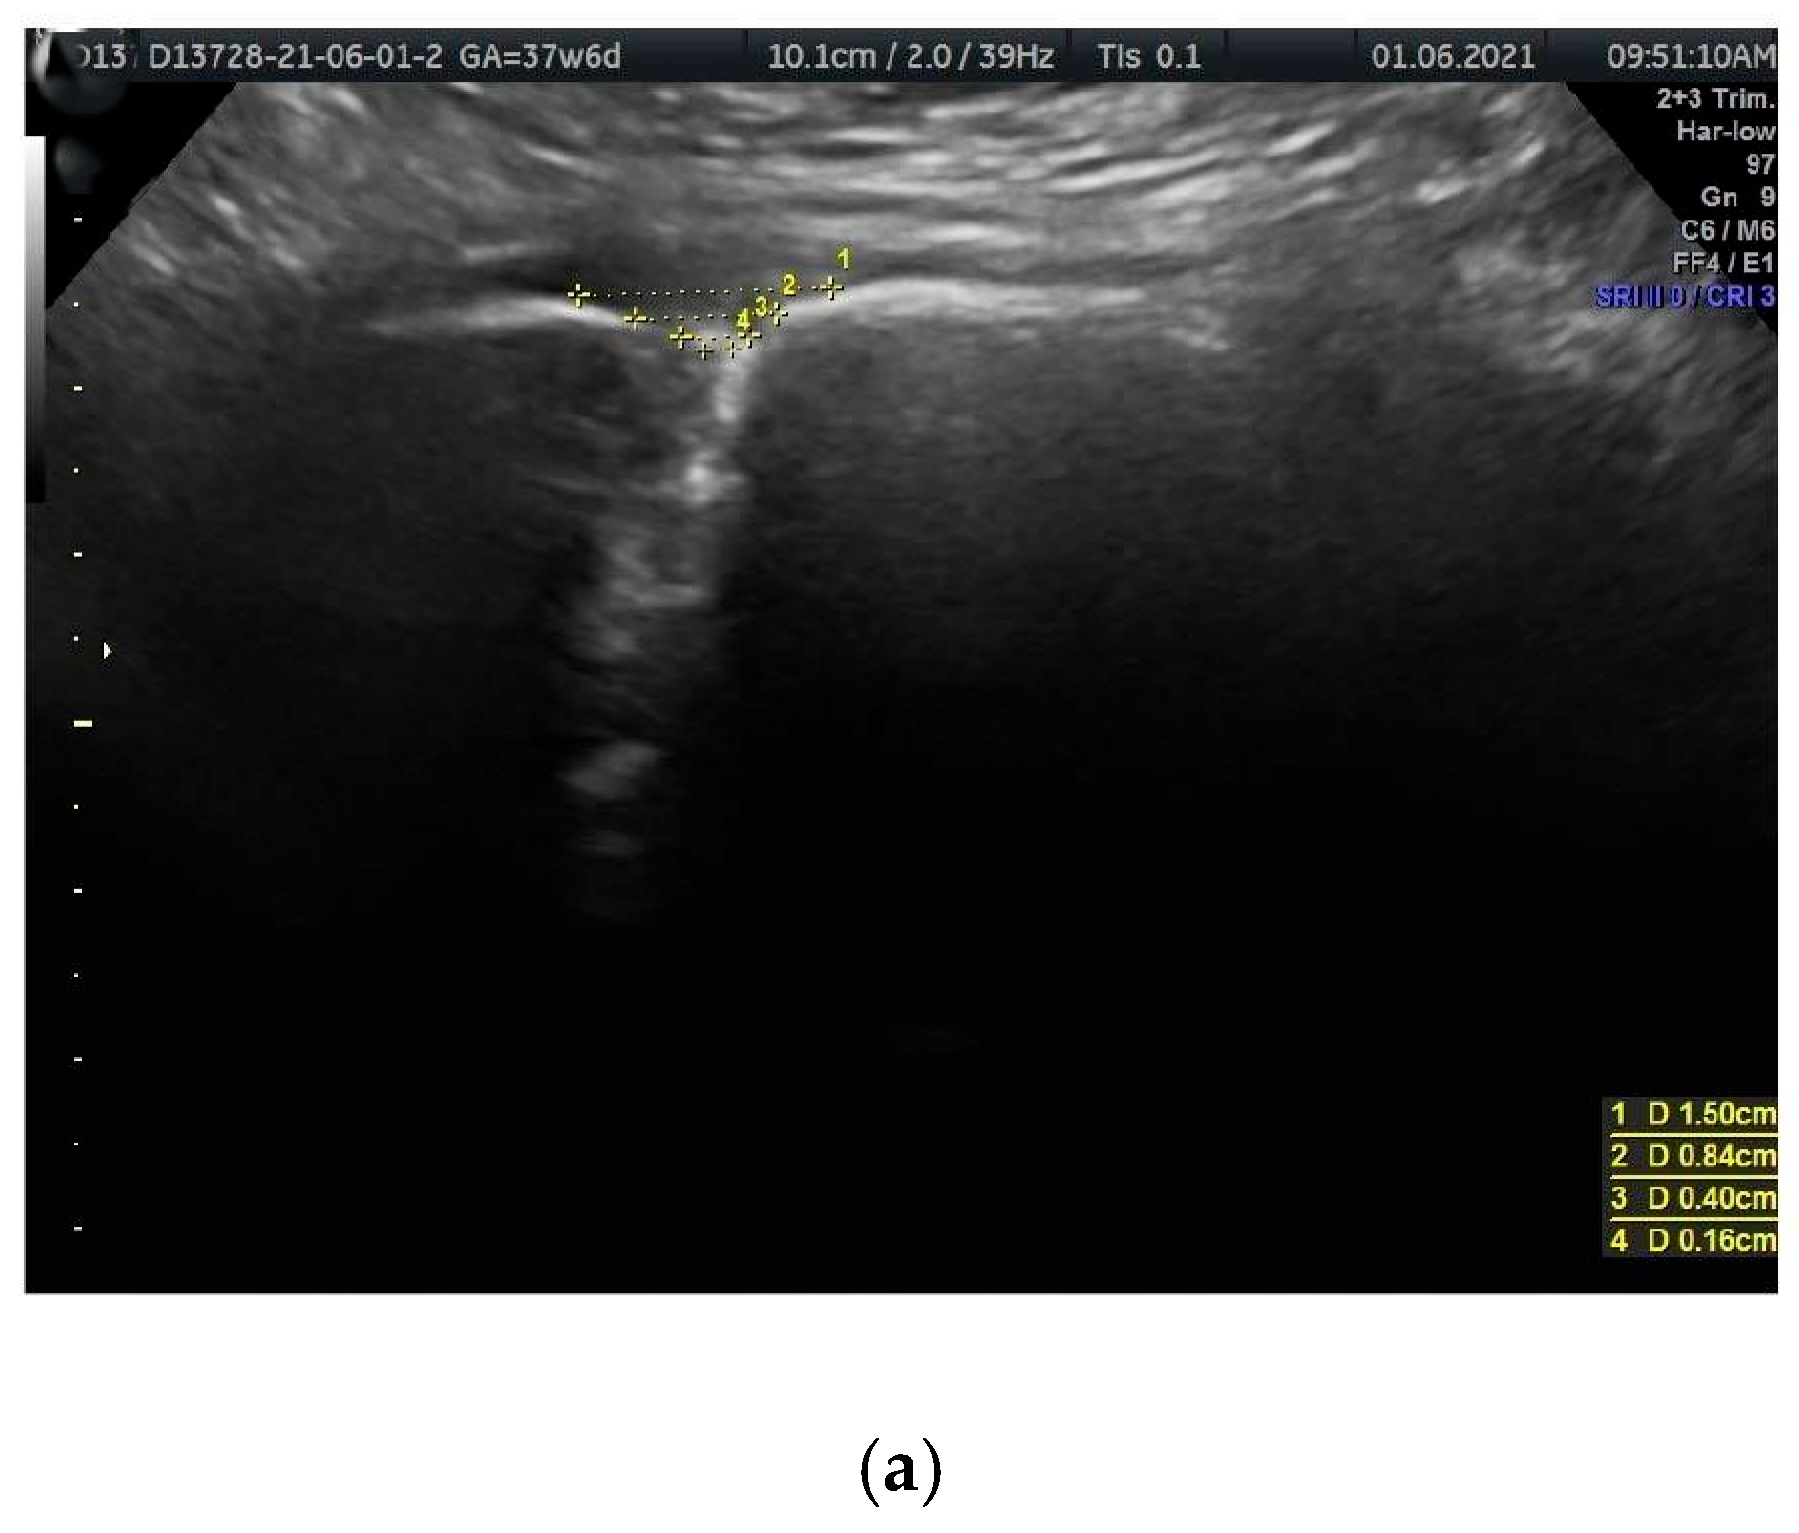

- PS entry middle width (PSemw): The distance measured at the midpoint of the PS entrance.

- PS width (PSw): The span between the right and left symphysial surfaces, measured at the midpoint of the PS. Another term for this is the PS width across the PS.

- PS depth (PSd): The distance between the proximal and distal borders of the PS disc.